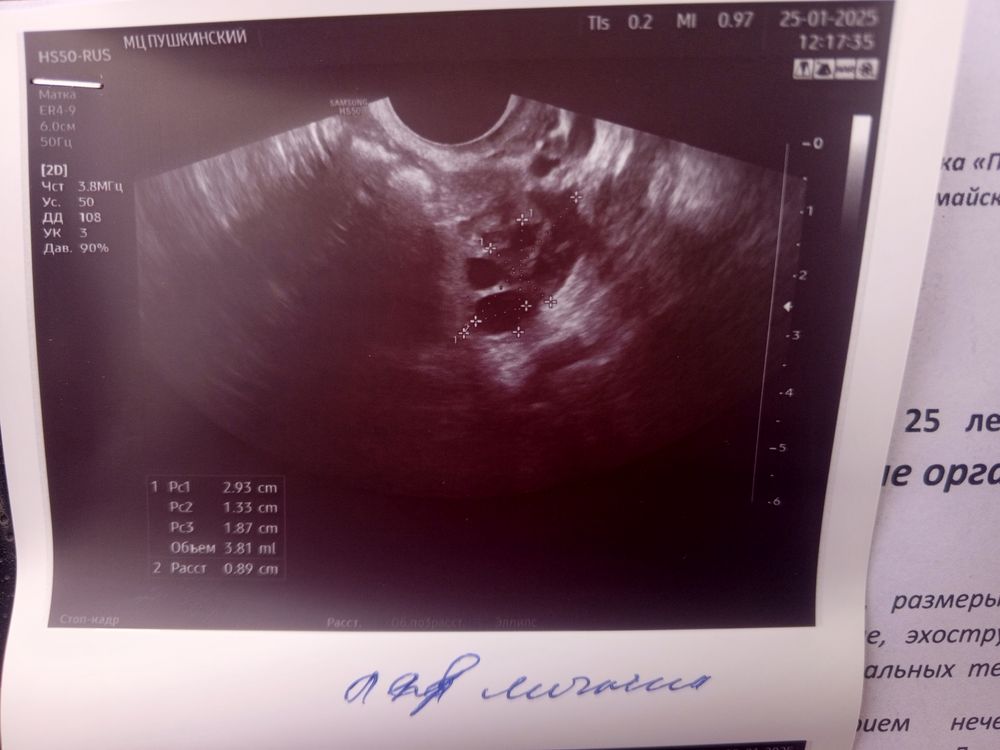

Аня, Изображение Изображение Изображение

Светлана , вот смотрите первая и вторая фаза, мне кажется у вас не было овуляции и эндометрий на 1 фазу, т.к. видно линию смыкания, но я не узист конечно, просто уже за кучу узи у себя различаю Изображение Изображение

Аня, вот это как я понимаю эндометрий или нет? Изображение